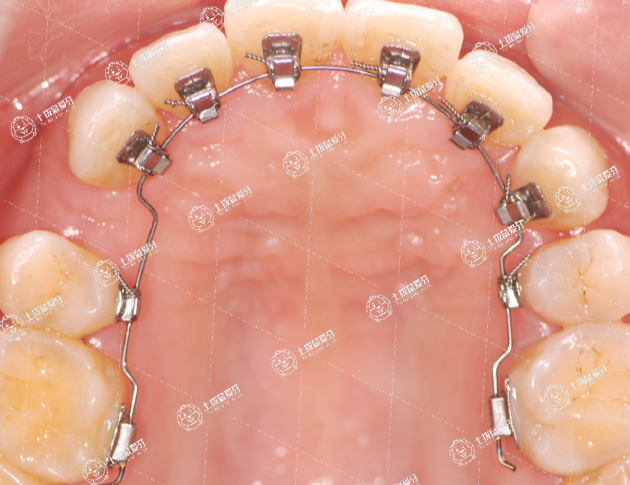

舌側(cè)矯正適用于對美觀要求較高的患者。由于正畸托槽和弓絲都在牙齒的舌側(cè),所以舌側(cè)矯正對于口腔內(nèi)的衛(wèi)生條件要求較高,患者要有口腔清潔的能力,和較好的口腔衛(wèi)生習(xí)慣。此外齲病和牙周病的易感人群,以及舌對異物十分敏感的人群應(yīng)謹(jǐn)慎選擇舌側(cè)矯正,可以選擇隱形可摘矯治器或舌側(cè)矯治器替代。

舌側(cè)矯正的隱形程度比較好,它是托槽和鋼絲安裝在牙齒內(nèi)側(cè),兼顧美觀和見效時間短的優(yōu)勢,同時也可以解決一些難度較大的牙齒畸形問題。